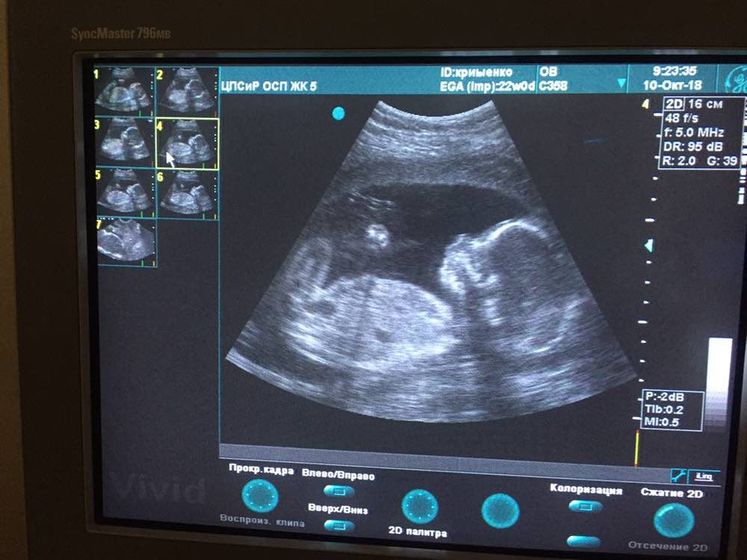

Сходили на узи, все нашли что потеряли неделю назад, вроде все хорошо. Но в заключении написали высокий риск задержки развития, я запереживала, скинула результаты подруге которая занимается скринингами платно, возможно буду переделывать там, пока жду что напишет. ИИИИ ????Похоже у нас снова будет доченька ???. Я счастлива) конечно и мальчику буду рада, но почему то девочка вызывает у меня умиление. С мужем думаем о женском имени, в приоритете Яна и Мия) он за первое я за второе) решим когда родится, если не передумаю ещё 100 раз) Еве тем временем сегодня 7 месяцев, вчера все поздравили, спасибо огромное)???. Естественно весь день провела в ЦпСиР и традиционные ежемесячные фотки не сделала, буду завтра этим заниматься. И для сравнения оба моих ребёнка на примерно одинаковом сроке. Первое фото Евы, второе — малыш в животике. По моему очень похожи))

Здорово, отличные новости, малышата похожи?